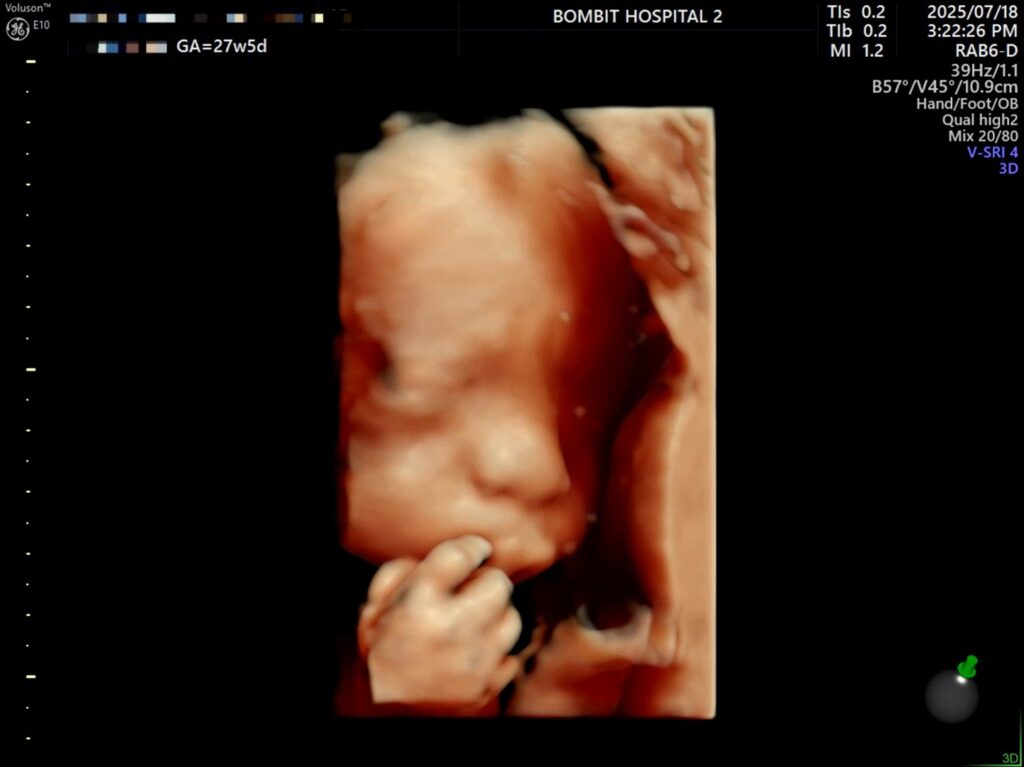

7월 18일, 27주 5일.

어제 단비의 입체초음파를 보았다.

초코우유도 못 먹는 몸인지라, 초음파실 샘이 권유한대로 물을 마시고 로비를 한 3바퀴정도 힘차게 걷고 나서 다시 초음파를 봤다. 단비가 여전히 엎드려있길래 선생님이 배의 특정 부분을 두드리셨는데(단비 미안).. 단비가 움직였다!

그렇게 다행스럽게도 단비 얼굴을 볼 수 있게 되었다.

– 처음에 보여준 귀.. 귀욥

– 통통한 손가락

입초로 본 단비 얼굴은 정말 너무너무 귀여웠다!! 보면서 코가 복코같이 눌려있다고 생각했는데,, 선생님은 아기 콧대가 높다고 했다. 엄마를 닮아서 그런 듯(?)ㅋㅋㅋ